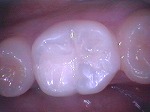

小児歯科

治療前に歯科器材や治療行為に慣れるためのトレーニングを行い、お子さんが泣かない、そして笑顔で治療が終えられるように心がけています。ただし外傷・歯髄炎・根尖性歯周炎など痛みを伴う緊急時は、トレーニングを行いながらの治療は難しい場合もあります。また永久歯に萌えかわる時期は、むし歯になりやすいため予防処置(フッ素塗布等)・シーラント(予防填塞)をおすすめします。

~シーラント~

術前

術後